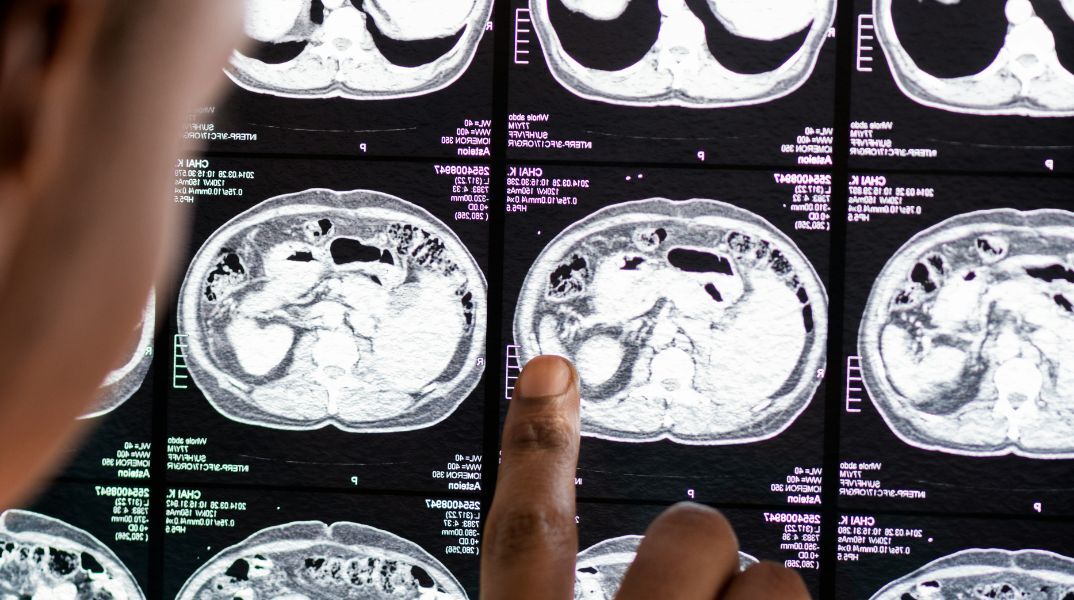

Για τους καπνιστές χρειάζεται έλεγχος για τον καρκίνο του πνεύμονα ο οποίος ευθύνεται για τον μεγαλύτερο αριθμό θανάτων από καρκίνο παγκοσμίως. Ένας στους πέντε θανάτους από καρκίνο οφείλεται στον πνεύμονα. Ο καπνός είναι ο κύριος παράγοντας κινδύνου για καρκίνο του πνεύμονα, με οκτώ στους δέκα καρκίνους του πνεύμονα να αποδίδονται στο κάπνισμα. Δυστυχώς, η πλειονότητα αυτών των καρκίνων διαγιγνώσκεται σε προχωρημένο στάδιο, γεγονός που εξηγεί την κακή του πρόγνωση. Ο προληπτικός έλεγχος γίνεται με αξονική τομογραφία θώρακος χαμηλής δόσης (πέντε φορές λιγότερη ακτινοβολία από μια συμβατική αξονική τομογραφία) και χωρίς ένεση ιωδιούχων σκιαγραφικών. Αυτός ο έλεγχος πρέπει να συνδυάζεται με τη διακοπή του καπνίσματος. Μελέτες δείχνουν ότι ο συνδυασμός του ελέγχου και της διακοπής του καπνίσματος μειώνει τον κίνδυνο θανάτου κατά 20%. Αν κάποιος είναι 50-74 χρόνων και καπνίζει ένα πακέτο την ημέρα, εκτός του ότι πρέπει να πάψει να καπνίζει, πρέπει να φροντίσει να δει την κατάσταση των πνευμόνων του και το πώς εξελίσσεται: απαιτείται δηλαδή σύγκριση υπερηχογραφικών εξετάσεων κάθε χρόνο —κι αν δεν υπάρχουν ανωμαλίες, οι απεικονιστικές εξετάσεις μπορούν να πραγματοποιούνται κάθε δύο χρόνια.